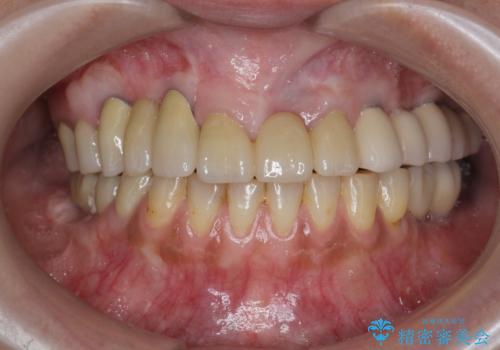

全顎的治療について

口腔内に歯の破折や歯周病、虫歯、欠損など複数の問題が存在する場合局所的に問題を解決していくのではなく全顎的な治療を行っていくことで長期的な予後を見込むことができます。